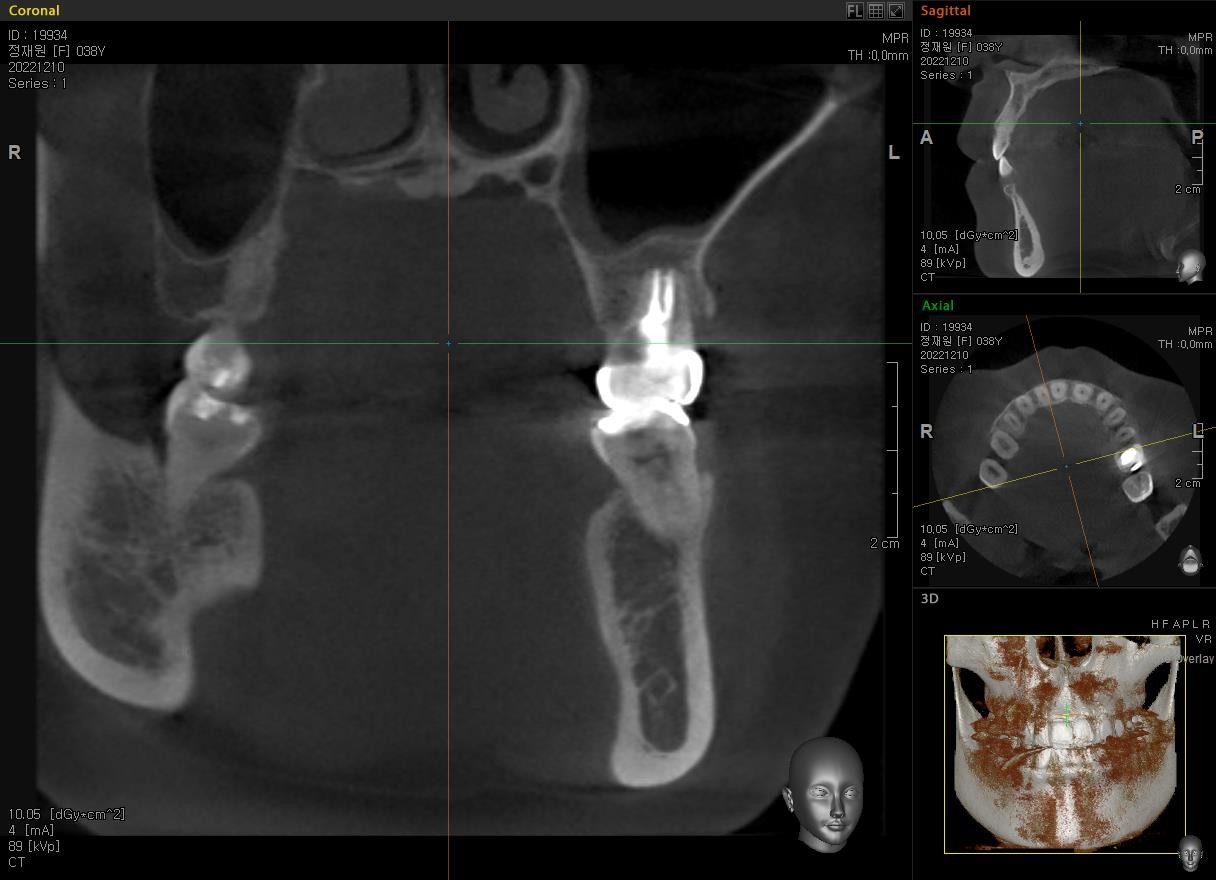

재근관치료

재근관치료 란?

재근관치료는 기존 신경치료가 실패한 치아를 최대한 보존하는 치료법으로, 치과의사의 숙련도와 치아 상태에 따라 성공률이 달라질 수 있습니다. 치아 보존을 우선한다면 임플란트보다는 재근관치료를 먼저 고려하는 것이 일반적입니다